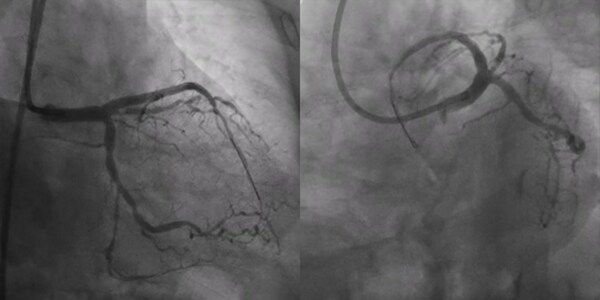

術(shù)前冠脈造影:

造影顯示中間支近段90%狹窄,LAD齊口完全閉塞,RCA近中段管腔不規(guī)則,最狹窄處80%,可見(jiàn)明顯側(cè)枝。

最終造影

造影顯示TIMI 3級(jí)血流,支架擴(kuò)張充分,IVUS顯示支架貼壁良好,遠(yuǎn)段無(wú)并發(fā)癥,手術(shù)成功。患者手術(shù)當(dāng)天順利出院,便可恢復(fù)正常生活和工作。